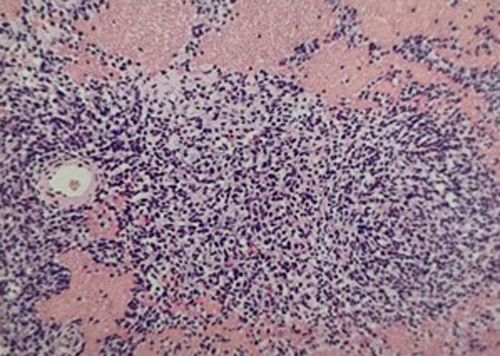

病理検査

腫瘍の一部、または全部を切除したものを検査します。

症例:胸腔内腫瘍(縦隔型リンパ腫)